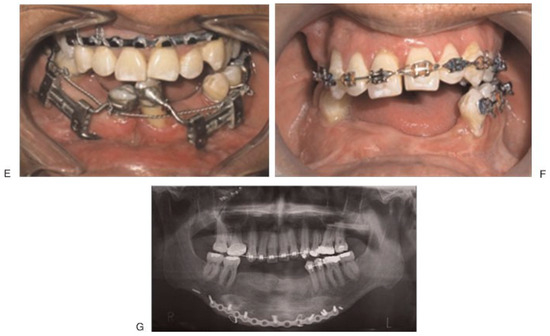

All patients signed a consent form to perform the surgical procedure and the use of the photographic material for academic purposes. Simple radiographic facial images were obtained for all the cases, as well as computed tomography scans with the three-dimensional reconstruction to visualize the size and degree of the alveolar defect and to plan the placement of devices. Three of the patients with cleft palate and lip aftermath presented an active oronasal fistula at the time of entry. In all cases, dental impressions were obtained and the device was adapted to them in the laboratory, specifically on the teeth with the use of bands. The bone anchorage was adapted on loops prior to the surgical procedure (Figure 2). In only one case (case 2), an adaptation of the device was set up on the orthodontic devices, introducing one part of the device into the orthodontic tubes, fixed on the present teeth in the disk and the fixed segment. In one case (case 6), trifocal bone transport was done with different latency times and activation for every disk.

Figure 2.

(A–D) Modified Hyrax device (VEGAX) device adapted for alveolar bone transportation technique. (E) Osteotomy design. Parallel to the edge of the future docking site and the edge of the disk transport, taking at least two teeth within the disk. Before the distractor is placed without fixation for the design of the osteotomy (broken lines). (F) Distractor activation leading the transport disk to the docking site, showing newly formed bone and nonmobile area. Note the key activation screw bent at the tip for comfort.